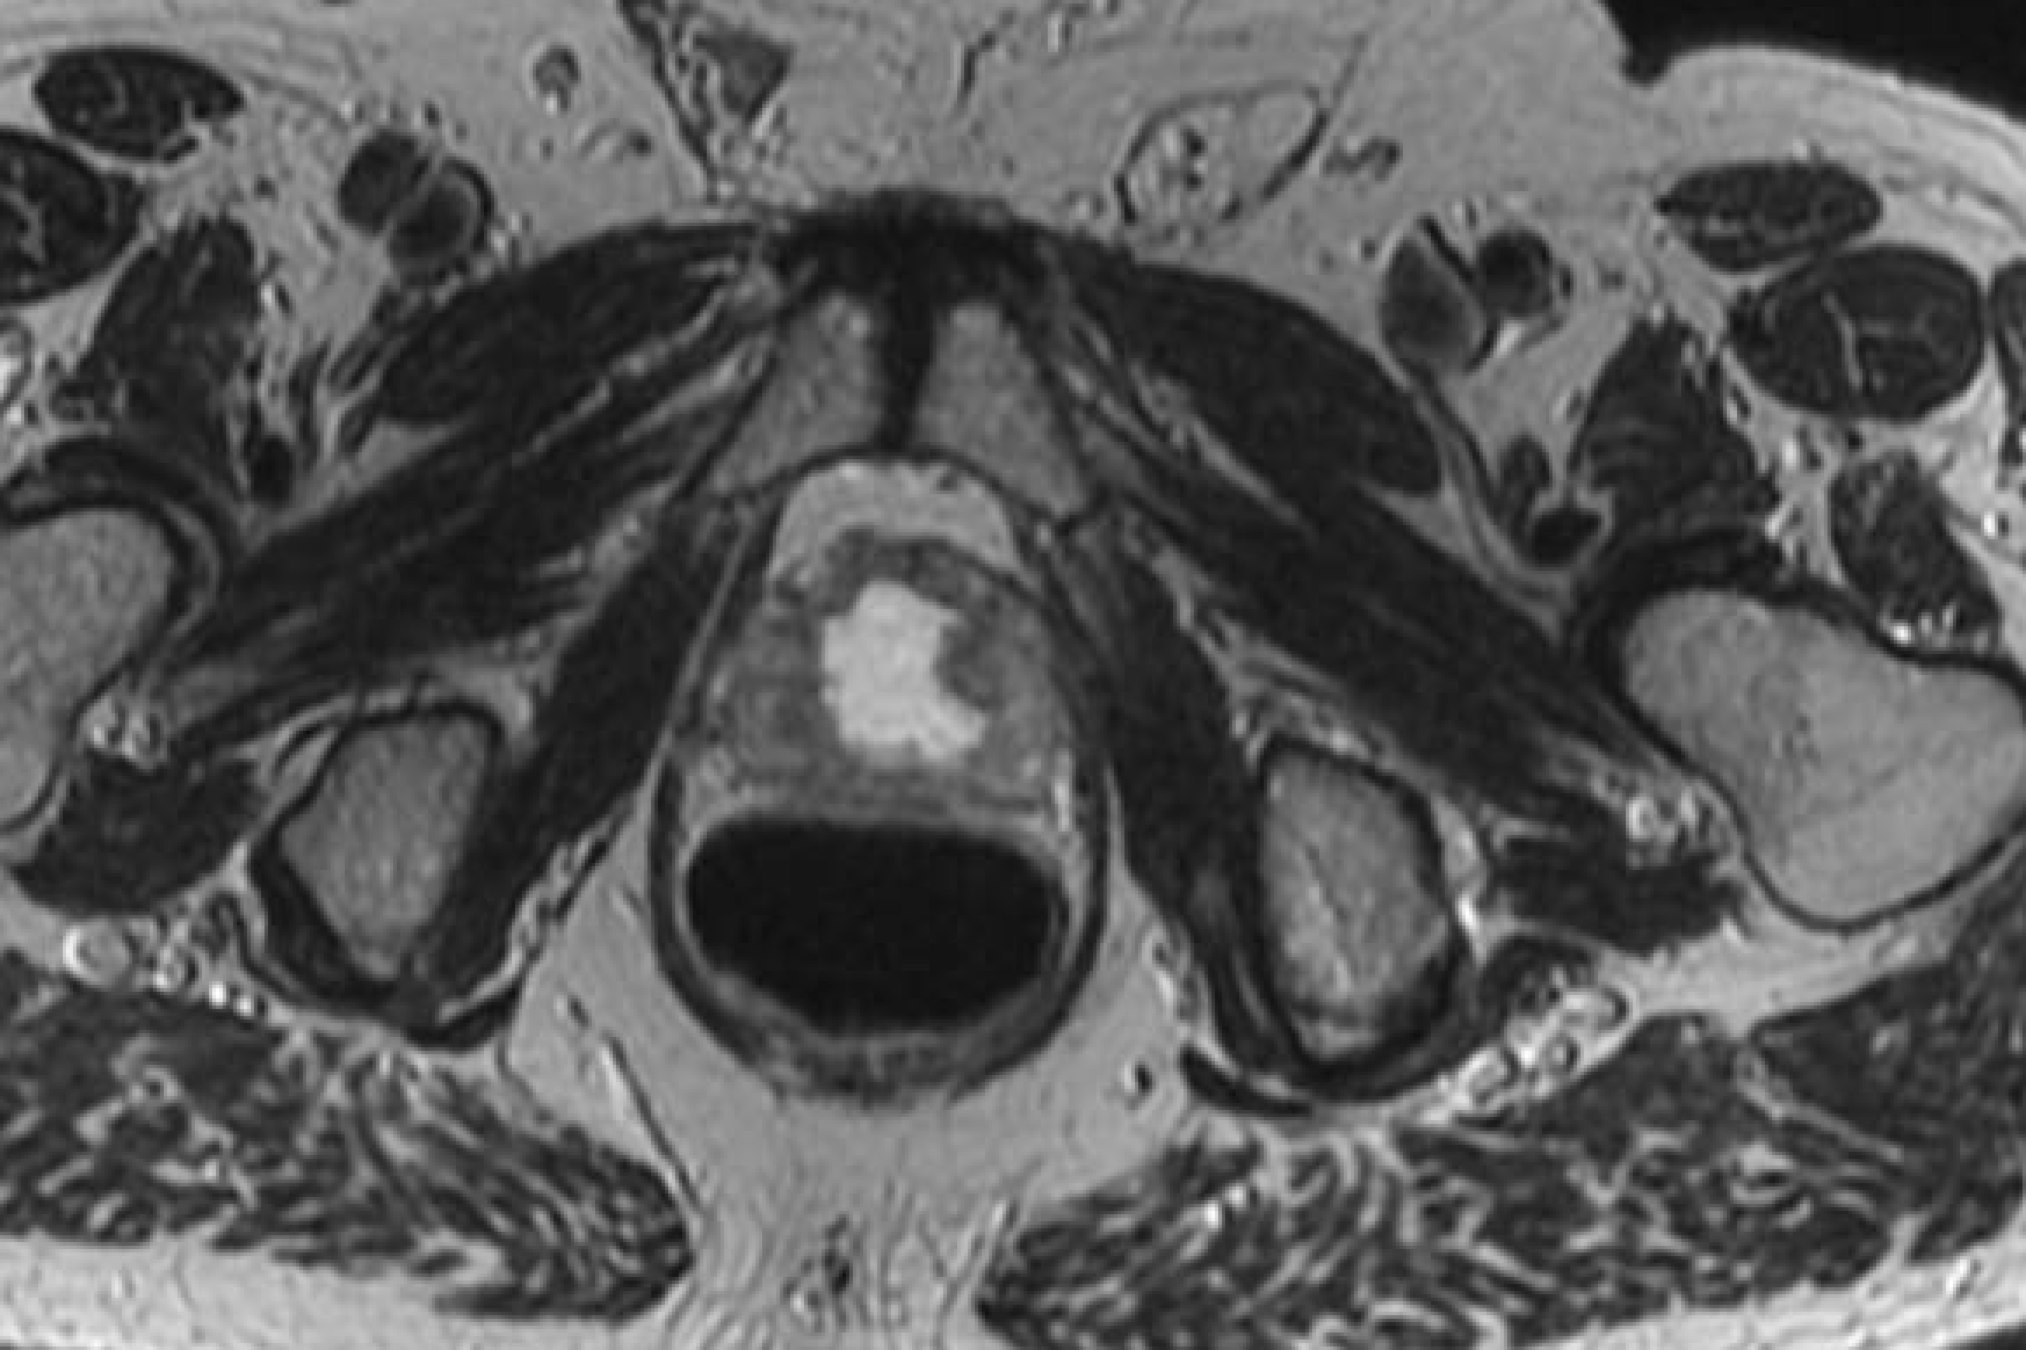

Anatomic delineation of the prostate and the apex using CT has not been without controversy. To attempt to resolve this several methods of identifying the apex were used:

Poor correlation of the prostate apex was found between these modalities. The retrograde urethrogram was tested to insure that the urethrogram itself did not displace the prostate by pre- and post-urethrogram MRI studies which demonstrated no artifactual displacement as a result of the urethrogram. Roach examined 10 patients and noted that the prostate volume was 32% larger on non-contrast CT than when determined by MRI. The regions of most non-agreement were posterior-inferior (neurvascular bundles) and posterior extent of the gland. The CT volume for prostate and seminal vesicles was 40% larger on the average than the MR with the CT variant 8 mm larger at the base of the SV and 6 mm larger at the apex. This was corrected for and persistent with interobserver variation.

There is significant variation of contours and techniques. The apex and base are regions most susceptable to variation. 3D perspectives help signficantly reduce this variation using transverse, sagital and coronal projections to determine the true extent of the prostate. More recently contouring atlases have been developed by the RTOG with grant assistance from the NCI and are available here. The following images are obtained from the RTOG contour atlases as an excerpt demonstrating areas of potential uncertainty.